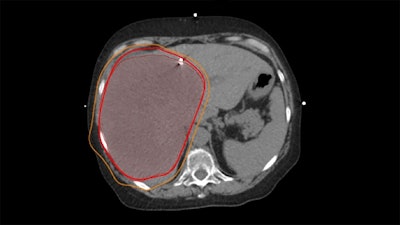

Sample radiation treatment plan demonstrating a 'supermassive' right liver tumor with planned radiation 'isodose lines' shown in bright red and orange.Sample radiation treatment plan demonstrating a "supermassive" right liver tumor with planned radiation "isodose lines" shown in bright red and orange.The University of Texas MD Anderson Cancer CenterAt a median follow-up of 17.9 months, survival rates were more than double in the combination group. Tumor-related liver failure rates were also significantly lower in the radiation group at 12.1%, compared with 47.1% in the chemotherapy-alone group. In addition, the treatment was well-tolerated, with no grade 4 or 5 adverse events recorded, the researchers reported.